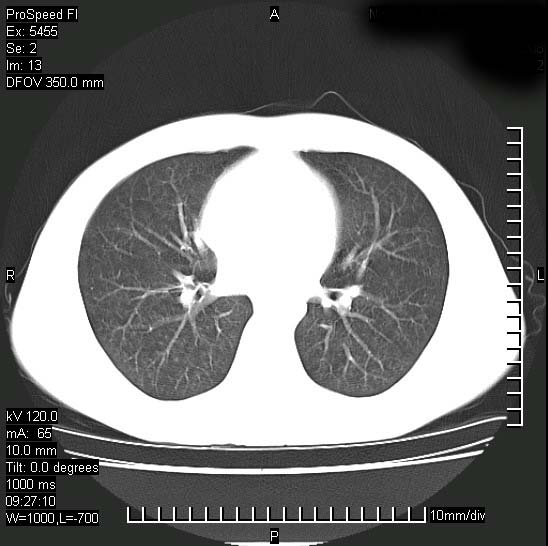

以下是引用zjzjr在2008-12-3 20:50:00的发言:[br]考虑泛细支气管肺炎,建议进一步检查除外肺出血性疾病如含铁血黄素沉着症、肺肾综合征等。

以下是引用zjzjr在2008-12-3 20:50:00的发言:[br]考虑泛细支气管肺炎,建议进一步检查除外肺出血性疾病如含铁血黄素沉着症、肺肾综合征等。

以下是引用光线在2008-12-3 20:19:00的发言:[br]双肺间质性改变。